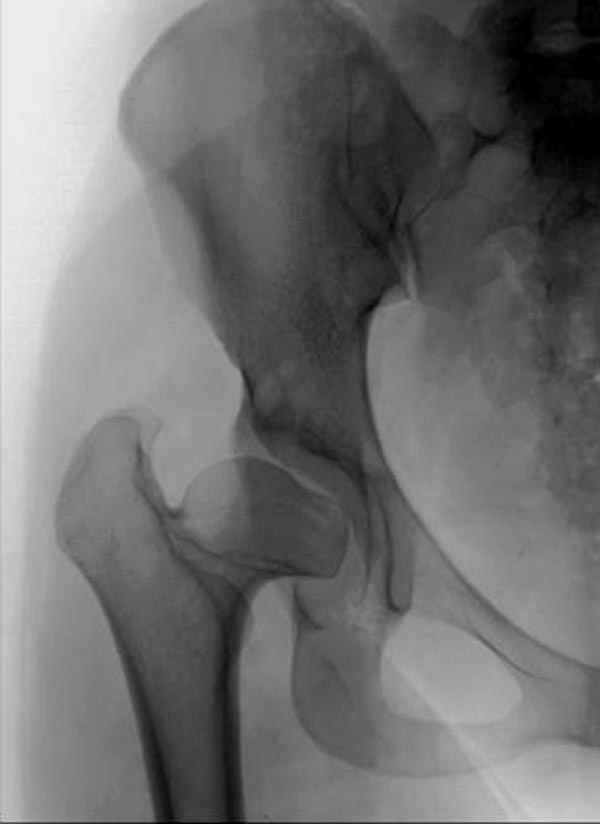

It appears that this patient has bilateral congenital hip displasia, as presented on the radiographs. As shown, the problem involves both sides of the hip joint: the acetabulum and proximal femur.

In this patient, it appears that addressing either the femur or the acetabulum will be insufficient to help correct this patient’s problem. It would be necessary to approach both sides of the hip joint to correct the hip dysplasia.

Depending upon surgeon preference, as well as availability of adequate operating room equipment and staff, this reconstruction can be done in two stages: periacetabular osteotomy with correction of acetabular retroversion would be the first stage. The second stage would involve a proximal femoral valgus osteotomy with neck lengthening.

In this second stage, a 120 degree blade plate can be used for correction proximal femur varus deformity. These procedures are both technically difficult, and require a great amount of pre-operative planning, both by the surgeons involved as well as the operating room staff.

Pic. 1-5 preop plan; 6-8 similar case